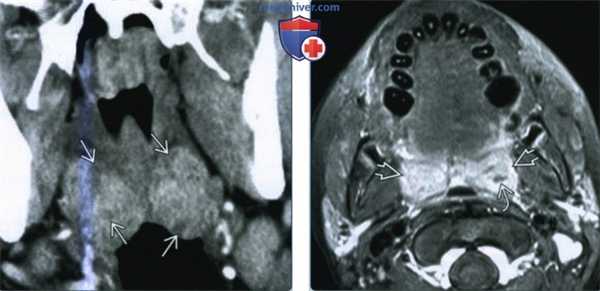

(Слева) При КТ с КУ в коронарной проекции определяется диффузное двустороннее увеличение небных миндалин, имеются участки неоднородной плотности, свидетельствующие об отеке. Явного абсцесса нет.

(Справа) При МРТ Т1 FS с КУ в аксиальной проекции определяется двустороннее увеличение небных миндалин с интенсивным накоплением контрастного вещества. Небольшие внутренние очаги пониженной интенсивности говорят о наличии подслизистого отека/экссудата.

(Слева) При КТ с КУ в аксиальной проекции визуализируется левосторонний МА и ПТА, распространяющийся через капсулу миндалины в заднее щечное пространство и медиальную крыловидную мышцу жевательного пространства. Отмечается накопление контраста в правой воспаленной миндалине, но данных за абсцедирование здесь нет.

(Справа) При КТ с КУ в аксиальной проекции наблюдается осложненный левосторонний МА больших размеров. Инфекционный процесс распространился в сонное пространство В, в переднелатеральном направлении в верхнее поднижнечелюстное пространство, в латеральном направлении в нижние отделы пространства околоушной железы.